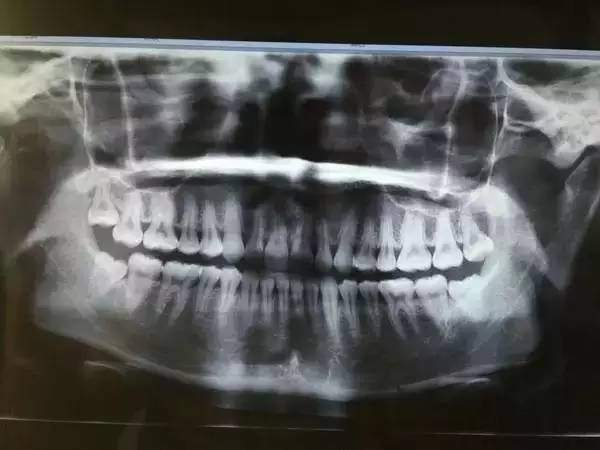

一般患者不自知,而由牙醫(yī)以X光確診得知。一般智齒萌生的空間缺乏,而會(huì)倒在第二大臼齒上,因而形成第二大臼齒清洗不易,乃至是牙齒部分吸收的表象,形成患者不舒服或牙疼。

640 (22).jpg

6、阻生齒

一般這是最討厭的一種,牙醫(yī)會(huì)覺(jué)得很難搞定,但患者卻不一定有感受,因而忽略了。這一種類型的牙齒,一般埋在齒槽骨的里邊,假如會(huì)痛,或是確診會(huì)有病灶發(fā)作的時(shí)分,就需求拔除了。

640 (24).jpg